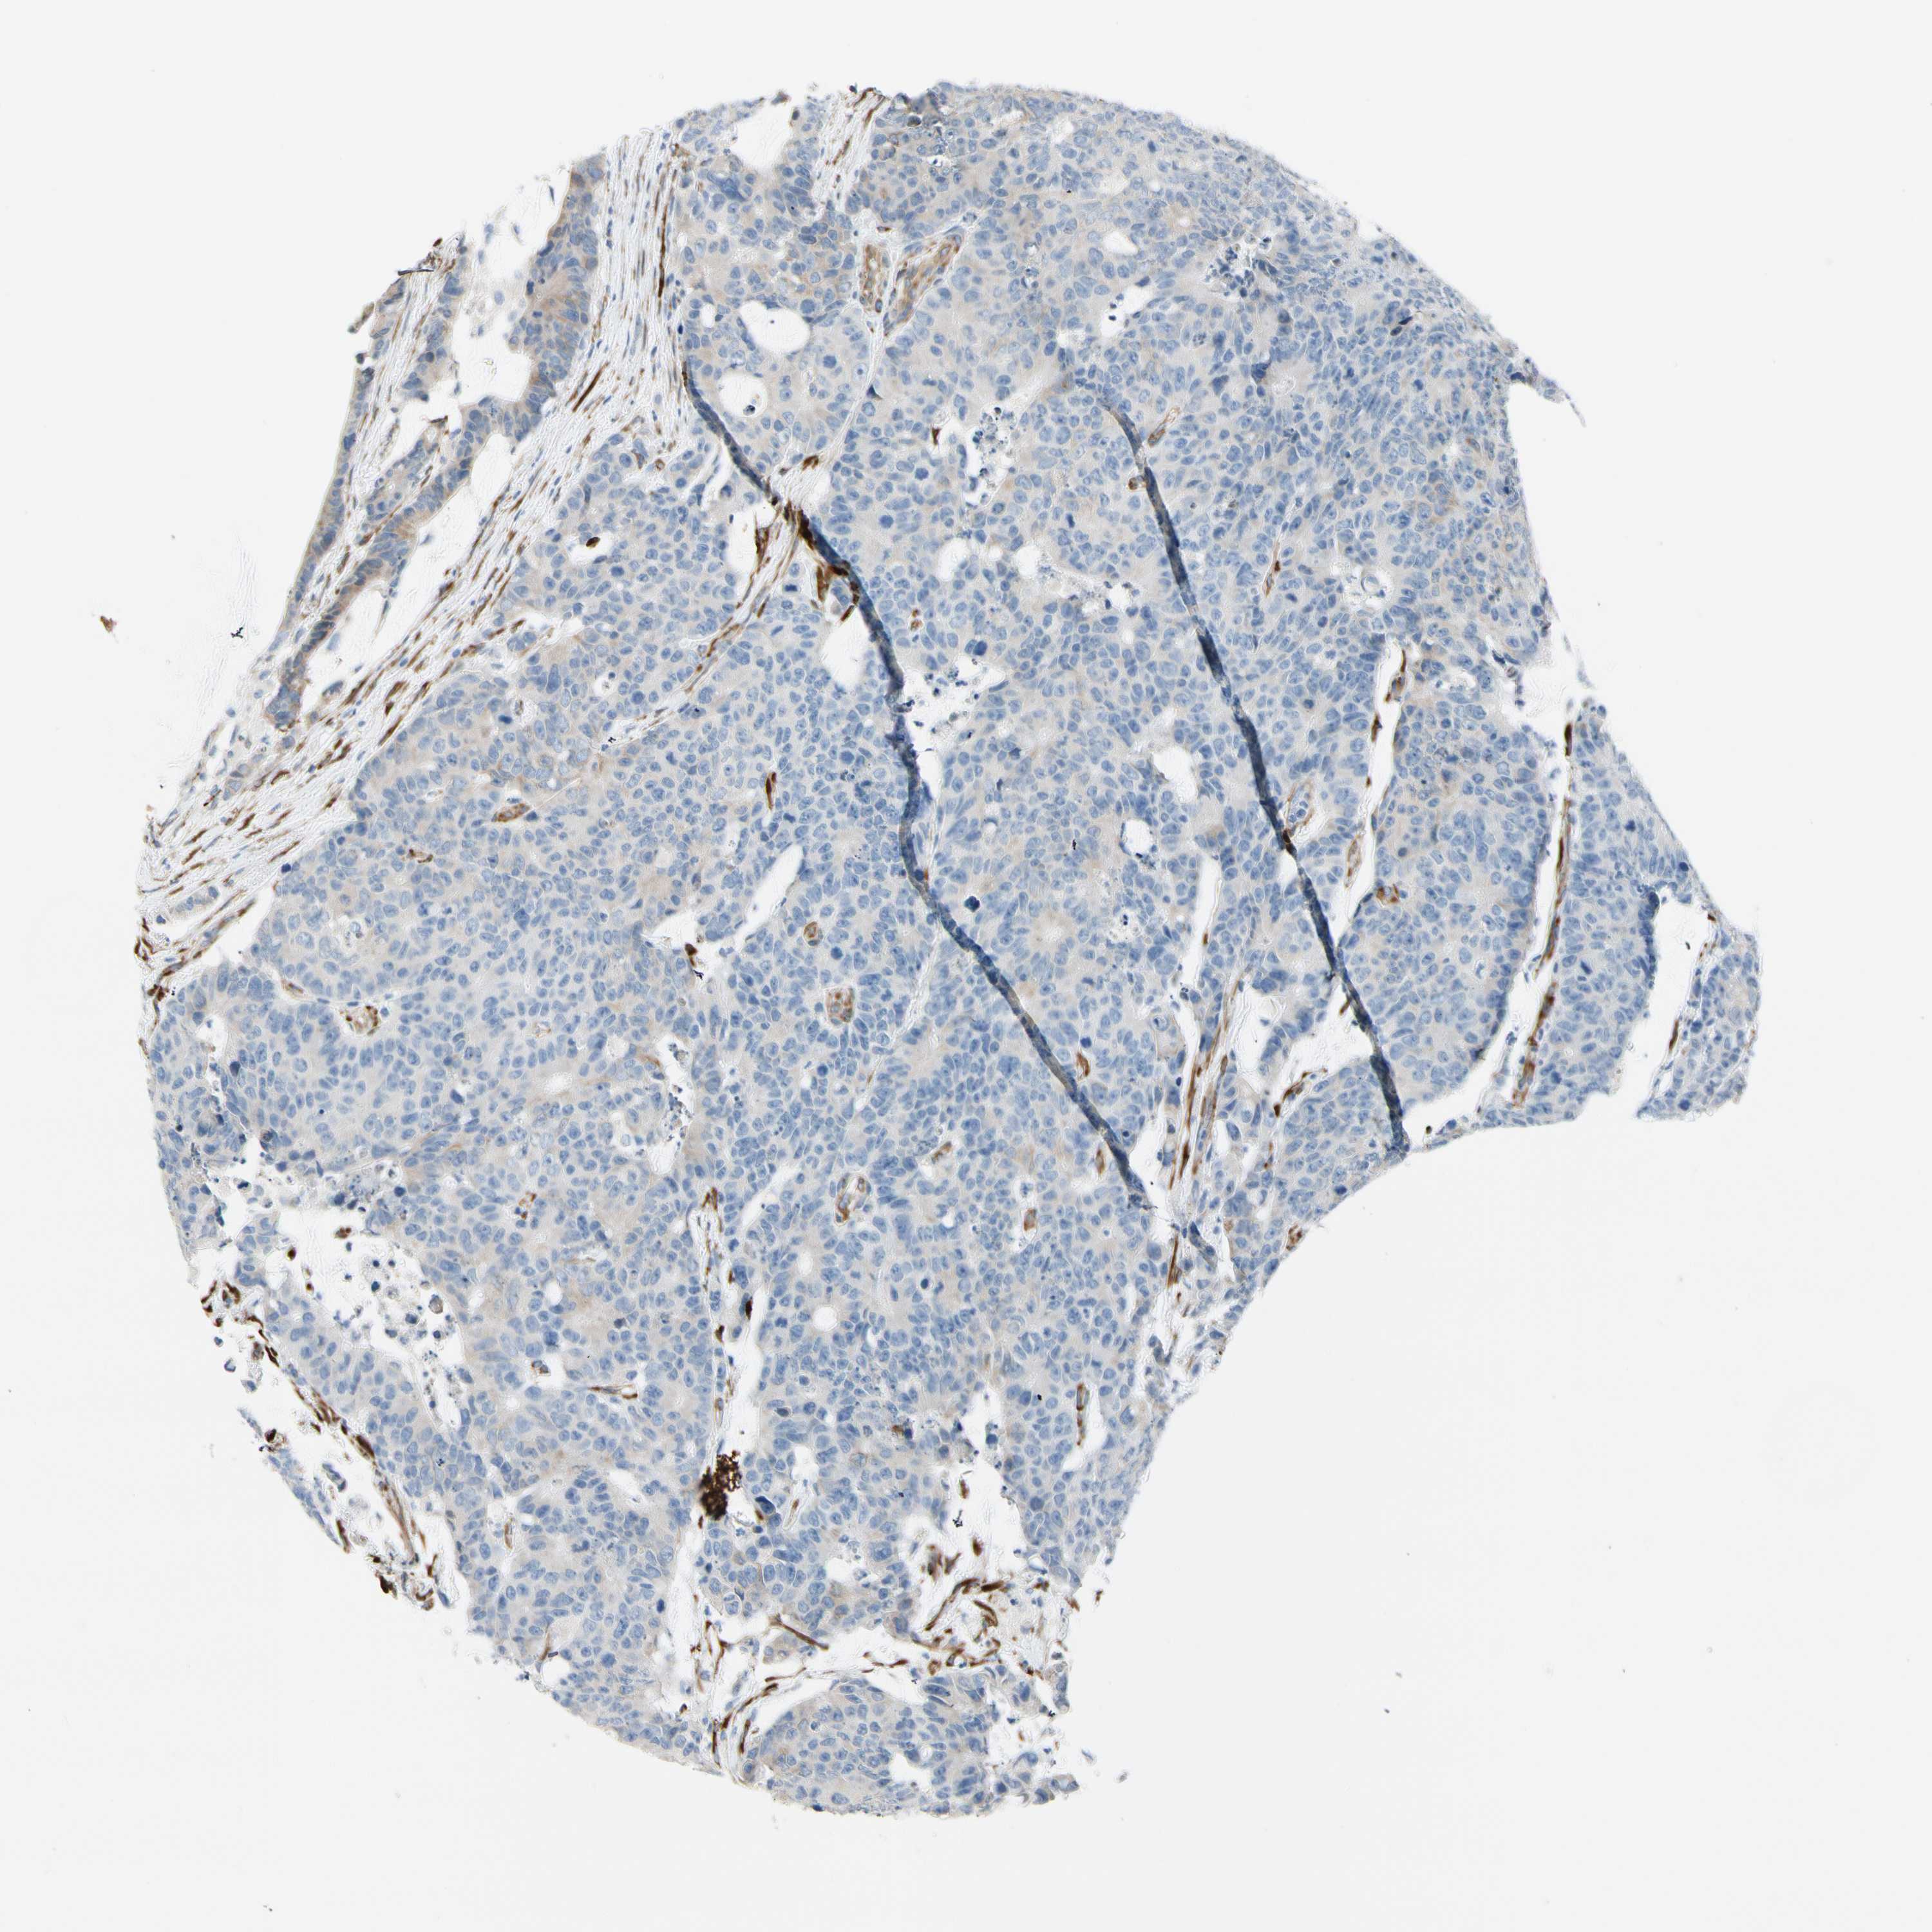

CANCER COLORECTAL CANCER Show tissue menu

Colorectal cancer

Human cancer

Colon adenocarcinoma